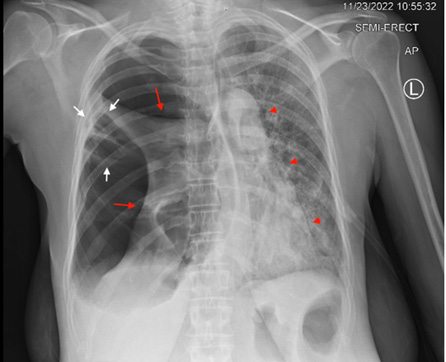

On day 2 of admission, the patient was comfortable still on supplemental oxygen to address the atelectasis and morning vital signs were all within normal limits. On routine bedside chest exam was done and yielded righ-sided, harsh, bronchial breathing and hyperresonance on percussion that were not present on admission. These findings prompted an emergent chest x-ray which showed a massive right sided pneumothorax with right lung atelectasis and mediastinal shift to the left. Ath that time, the surgery service was consulted and a pigtail chest tube was placed. Post-tube-placement chest x-ray suggested an initial slight improvement of the pneumothorax. However, after two days with her chest tube intact, serial chest x-rays failed to show any appreciable improvement of the size of the pneumothorax. To further investigate the persistence of the pneumotorax, a thorax CT was ordered and showed confluence of the lower border of the cavitary lesion with the right pleural space and tethering of tissue to the right sided chest wall pleura highly suggestive of an alveolarpleural fisutla (Figures 4-7).

Figure 4: Single view chest X-ray showing Right pneumothorax with collapsed right lung; Red arrows, and left mediastinal shift; red arrow heads. Persistent Cavitary lesion with tethering of right lung tissue to chest wall; white arrows.